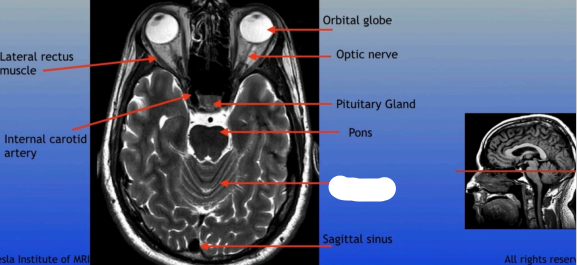

Lateral Rectus Muscle

Internal Carotid Artery

Orbital Globe

Optic Nerve

Pituitary Gland

Pons

Sagittal Sinus